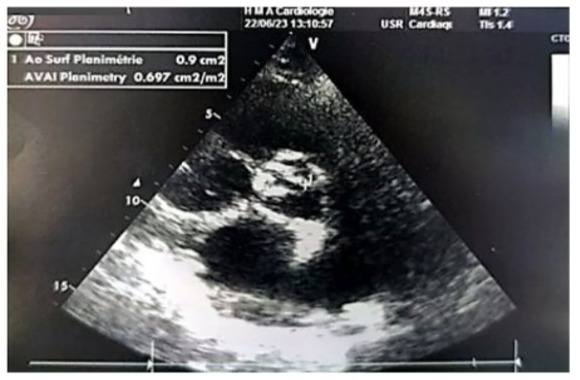

Figure 6: Parasternal short-axis echographic image showing a valvular area of 0.9 cm² by planimetry (indexed area of 0.7 cm²/m²).